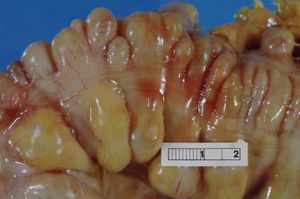

| الأمعاء الغليظة (sigmoid colon) تـُبدي عدة رتوج. الرتوج البادية على جانبي حزمة العضلات الطولية (taenium). | |

ويتميز التهاب الرتج بوجود انتفاخات على الجدار الخارجي للقولون تُسمى الرتوج. ونادرًا ما يصيب التهاب الرتج الأشخاص الذين تقل أعمارهم عن الثلاثين عامًا. ولاتظهر أية أعراض على معظم المصابين بالتهاب الرتج. وقد ظل الأطباء لسنوات عديدة يعتقدون أن الوجبة الغذائية المحتوية على نسب قليلة من الخشائن (ألياف الفواكه والخضراوات) قد تساعد في منع التهاب الرتج، غير أن الشواهد في هذه الأيام قد أثبتت العكس إذ إن نقص الخشائن في الوجبة الغذائية يجعل الفضلات في القولون أكثر التصاقًا وأكثر لزوجة ولا تتحرك في القولون بسهولة. ويسبب ذلك ضغطًا ينتج عنه انتفاخ الغشاء الداخلي للقولون في العديد من النقاط الضعيفة، مما يؤدي إلى تكوين انتفاخات صغيرة دائمة، يمكن أن تُرى عن طريق الفحص بالأشعة السينية. ونادرًا ما تحدث هذه الحالة بين سكان البلاد النامية، ذلك لأن نسبة الألياف عالية في الوجبة الغذائية العادية عندهم.